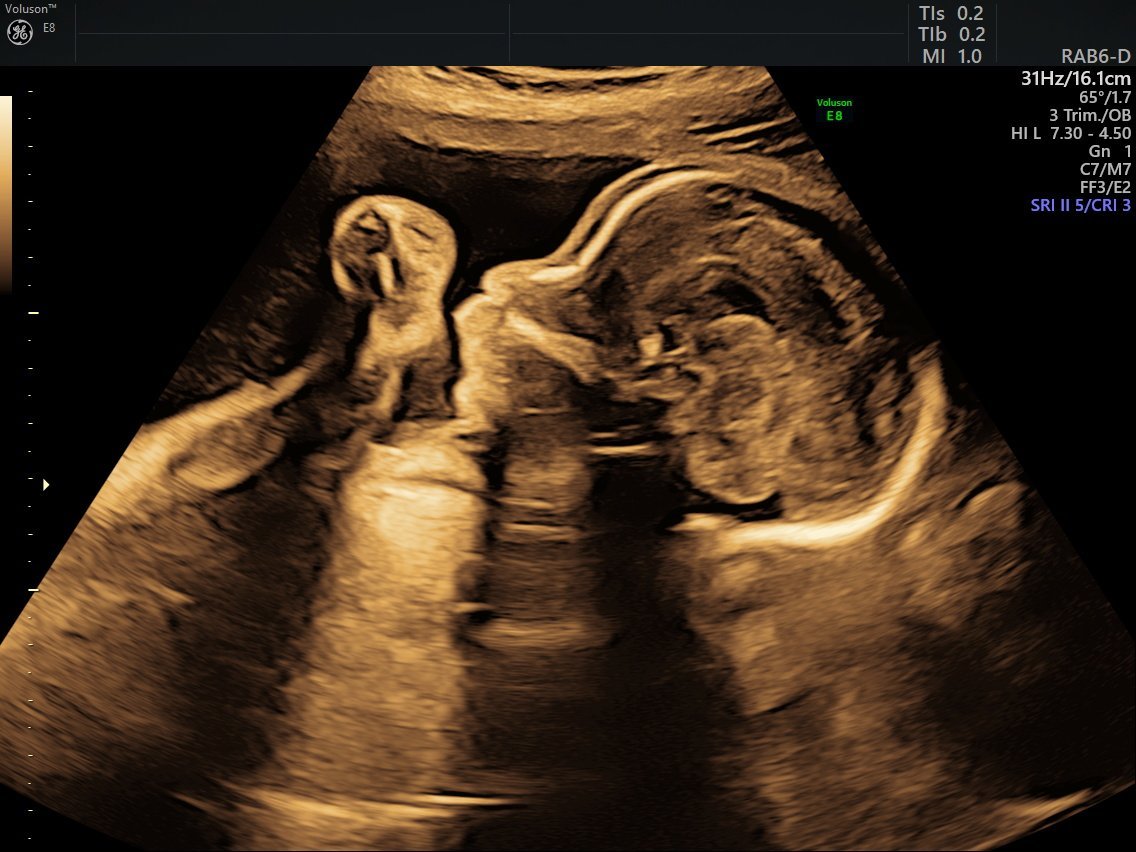

Ето ни и нас от вчера:

Аз не разбирам много от тълкуване на изображенкв, на профила малката е с отворена уста май, тя и не стоеше много мирно по време на снимките и нямаме топ кадри. На мен всички ваши ми изглеждат супер. ✨